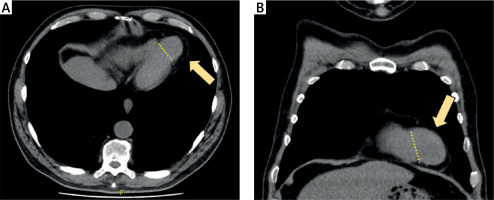

Figure 2

Computed tomography (CT) scans depicting the left ventricular aneurysm. A – Transverse plane section highlighting the ventricular aneurysm. B – Coronal reconstruction providing a detailed view of the aneurysm morphology